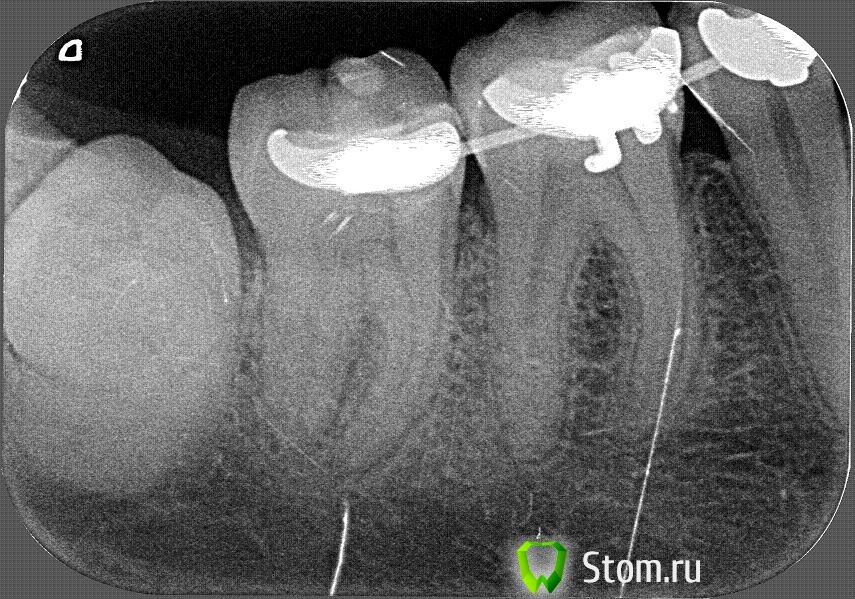

Anna_M Опубликовано 25 января, 2012 Поделиться Опубликовано 25 января, 2012 (изменено) Здравствуйте, уважаемые специалисты! Очень нуждаюсь в вашей помощи и подсказке. Болит 46 зуб. Предыстория: зуб был пролечен и запломбирован по поводу кариеса лет 15 назад. С тех пор не беспокоил. В 2005 году была установлена брекет-система с кольцами на 6-ках. Через год, в 2006, кольцо на 46 расцементировалось, стало болтаться, с этого момента зуб просто адски разболелся, стал сильно реагировать на многие раздражители: холодное, горячее, сладкое, когда кольцо шевелилось, тоже было больно. В общем, пошла лечить. Зуб запломбировали. Кольцо приклеили заново. Боль значительно уменьшилась, от всех ощущений осталась только реакция на холодное. Врач сказал, что зуб пролечен нормально и в этой остаточной реакции нет ничего страшного.С тех пор реакция на холодное так и не прошла. Она то появлялась, то исчезала, в большей или меньшей степени. В принципе, было терпимо. В 2010 г. с наступлением зимних холодов 46 зуб внезапно проснулся, стал очень сильно реагировать на холод, даже если просто выйти на улицу. После воздействия холода долго ныл, буквально часами. Плюс стал ныть и просто к ночи. Конечно же, я пошла к врачу. Сделав снимок, терапевт принял решение зуб не трогать, т.к. «зуб замечательный, пломба тоже». После этого я задала вопрос об этом зубе здесь на форуме. Мне подсказали, что, возможно, судя по снимку, во время того пломбирования в 2006 г. был вскрыт рог пульпы, и мне нужно искать хорошего эндодонтиста. В нашем городе найти его было очень непросто. Пока я занималась поисками, холода прошли, зуб успокоился, осталась малоприметная реакция на холод, но я настолько к ней привыкла, что уж и не обращала внимания. Тем временем была повторно установлена брекет-система, на этот раз лингвальная. Прошел год, снова наступили холода, и снова этот зуб активизировался. Стал ужасно реагировать на холод, долго-долго после этого ныть, периодически побаливал к ночи, из новых ощущений добавились кратковременные несильные «прострелы» (не знаю, как назвать их по-другому). К этому времени я нашла очень сильного эндодонтиста с хорошими рекомендациями и с микроскопом. Итак, в ноябре 2011 (буквально 2 мес. назад) я пошла к нему на прием. Он сделал свежий снимок, проанализировал, сравнил с предыдущим, сказал, что на двух снимках – свежем и годичной давности - есть небольшое расширение в периапексе, но, вероятно, это связано с ортодонтическим лечением, прошлым и нынешним. Никаких изменений в периодонте за год не произошло, динамики нет, из чего следует, что расширение – следствие ортодонтии. Осмотр в кресле выявил реакцию на холодный воздух. Перкуссия безболезненная. ЭОД и холодовой тест эндофростом не проводили. Справедливости ради надо отметить, что рядом стоящие 43, 44 и 45 тоже реагировали на холодный воздух, т.к. на них есть клиновидные дефекты, которые я планирую закрывать после ортодонтии с помощью периопластики. Но я могу четко отдифференцировать реакцию 43-45 на холодовой раздражитель, т.к. она резкая и очень кратковременная, в отличие от реакции 46, которая не так резка, но гораздо более длительна. Чтобы узнать, вскрыт рог пульпы, или нет, доктор решил снять пломбу и рассмотреть все под микроскопом. Сделал два укола анестетика по бокам зуба длинной иглой под углом куда-то глубоко в кость. Сказал, что это хороший метод анестезии, при котором не онемеет пол-лица, а обезболится только зуб… Анестезия совсем не подействовала. Врач сверлил, дул воздухом и поливал водой, как говорится, «наживую». Было очень больно По моему лицу он понял, что больно, доколол еще… Не подействовало. Доктор сказал, что анестетик не дошел до нерва из-за того самого расширения в периодонте. Продолжили так. В итоге, посмотрев под микроскопом, доктор сказал, что никакого намека на вскрытую пульпу тут нет, и закрыл все пломбой. После процедуры сказал, что боль, которую я чувствовала во время лечения, - хороший признак, это значит, зуб живой. С этого момента реакция на холод усилилась. Зуб реагирует уже даже просто на воду комнатной температуры и долго после этого ноет, а если выйти на мороз, то вообще труба. Добавилась неприятная реакция на горячее. Порой эта нудная боль настолько выматывает, что хочется немедленно записаться на прием и депульпировать, наконец, этот многострадальный зуб. Волнует один момент. У меня брекеты инкогнито, которые нельзя переклеивать в силу конструктивных особенностей. Еще во время предыдущего визита доктор сказал ассистенту: «Видишь, тут инкогнито, кламп никак не надеть» и работал, обложив зуб ватками. Если придется делать эндо, то как же быть с коффердамом? И, кроме того, ведь эндодонтист уже осматривал зуб, свой вердикт по нему вынес: пульпита нет, рог не вскрыт, зуб живой, в эндодонтии необходимости нет… В общем, у меня несколько вопросов к вам, дорогие специалисты: 1) что все-таки с 46 зубом: пульпит, или не пульпит? 2) если пульпит, можно ли отложить эндо до снятия брекетов (оно произойдет месяцев через 6-8, ориентировочно). Боль я смогу потерпеть. Мне не впервой, в общем-то. Брекеты приучили к разного рода зубной боли . Главное, чтобы была понятна причина и ясна цель, в этом случае с болью можно смириться. 3) если не пульпит, как избавиться от всех болезненных симптомов и в чем их причина? 4) тот снимок, который сделал врач два месяца назад перед вскрытием пломбы, мне не отдали на руки, поэтому я сегодня сделала в другой клинике свежий прицельный. С этого ракурса стал виден 47 зуб. На нем сверху, на жевательной поверхности, виднеется темное пятнышко, не кариес ли это? И не он ли является причиной всех моих мучений? Может такое быть, что боль от кариеса на 47 иррадиирует в 46 и путает диагностическую картину? Буквально три дня назад с 47-го зуба спилили ортодонтическую накусочную пломбу, которая весь год покрывала всю жевательную поверхность этого зуба и была налеплена поверх обычной терапевтической пломбы, сделанной тоже лет 15 назад. Может ли быть такое, что под этой ортодонтической накладкой развился кариес, который никто не заметил из-за того, что это место было полностью ею закрыто и кариес не визуализировался при осмотре? Прикрепляю снимки: 1. годичной давности 2. свежий сегодняшний 3. на всякий случай прикреплю ОПТГ для полноты картины (орто не слишком свежее, конечно, июль 2011, но хоть что-то). Изменено 25 января, 2012 пользователем Anna_M Ссылка на комментарий

Scrabble Опубликовано 25 января, 2012 Поделиться Опубликовано 25 января, 2012 (изменено) Судя по описанию-пульпит, и давний. Боли на горячее говорят о том, что коронковая пульпа мертва. Мезиальный рог пульпы высоко расположен, пломба очень близко. Если сообщения нет-это не показатель, микробы через тонкую стенку дентина проникают. А 46 или 47-это надо во рту смотреть, и с холодовой пробой. Изменено 25 января, 2012 пользователем Scrabble Ссылка на комментарий